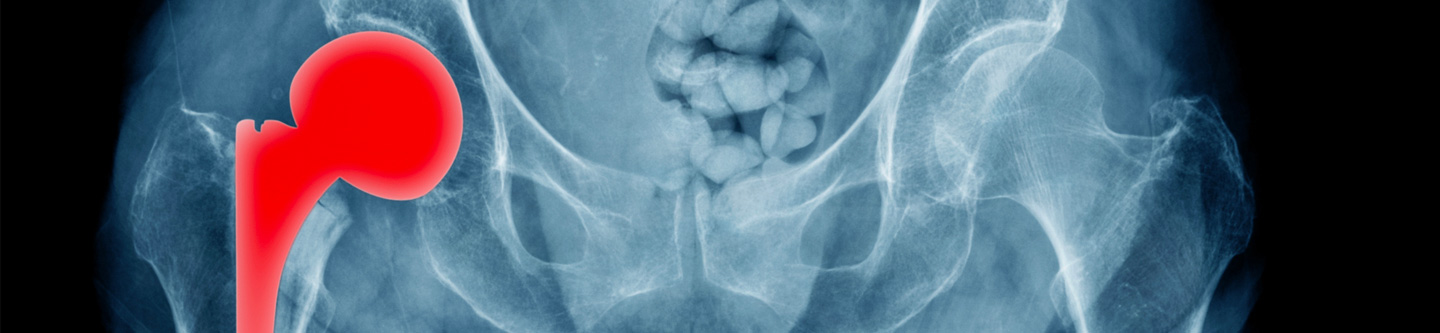

The physicians at First State Orthopaedics have extensive experience and knowledge in the diagnosis, treatment, and management of all conditions of the hip, knee, and shoulder. Our fellowship trained surgeons specialize in the replacement of joints affected by arthritis, inflammatory conditions, and trauma. From preoperative education, through surgery, recovery, and rehabilitation, everything is designed for the special needs of our patients.

Our joint reconstruction team is at the forefront of outpatient total shoulder replacement, reverse shoulder replacement, total hip replacement, partial knee replacement, and total knee replacement.  Our surgeons are proficient in all approaches for joint replacement, including direct anterior hip replacement.  The First State Surgery Center is equipped to allow our surgeons the ability to perform procedures which safely allow patients to now recover in their own homes.

• Total hip replacement